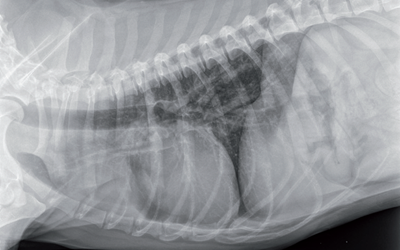

Photo 1 - Vue thoracique de profil

On note l’augmentation de densité en avant du coeur dans le médiastin crânial.

À cause de la masse on ne peut pas discerner s’il y a une augmentation du nœud lymphatique sternal.

Puis les radiographies thoraciques montrent une importante masse tissulaire dans le médiastin crânial crânial au cœur sur la vue latérale et s’étendant jusqu’à la gauche du cœur sur la vue ventrodorsale.

Il n’y a pas de signe de lymphadenopathie trachéobronchique. Ces images sont compatibles avec une masse thymique.